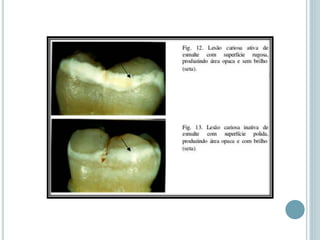

 Lesão cariosa ativa ou

aguda:

Considerada progressiva

2. Lesão cariosa inativa Mancha branca e brilhosa Desmineralização,

remineralização e lisura

3. Lesão cariosa ativa Mancha branca e opaca Desmineralização e

rugosidade

 Lesão cariosaativa ou aguda: Considerada progressiva CLASSIFICAÇÃO DAS CÁRIES